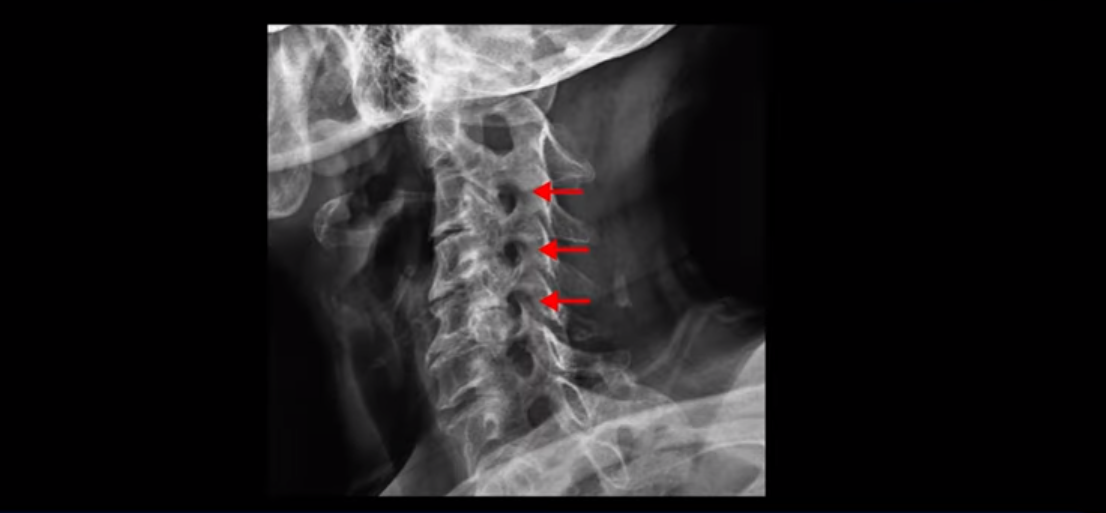

X-ray로 봐도 신경 구멍들이 좁아진 게 보입니다.

이런 걸 협착이라고 부르는 거죠. 이 분의 가장 불편한 증상은 20년간 아픈 만성적인 목통증과 어깨통증, 두통과 눈 통증인데 최근 들어 가증 불편한 증상은 목이 아예 돌아가지 않는 겁니다. 그래서 운전할 때도 사이드 미러를 보려면 몸을 돌리셨다고 하는데요. 주사 효과도 전혀 없고 대학병원에서도 디스크와 협착인데 그냥 약먹고 운동만 하라고 하면 이 환자는 어떻게 해야 할까요?

이 환자분도 아까 X-ray에서 보여드렸듯이 아주 심한 일자목, 거북목이 있고 그 결과로 목의 거의 모든 마디가 다 퇴행이 진행되어 있죠. 즉 거북목은 모든 목질환, 특히 목디스크, 목협착증의 어머니 질환이며 그래서 목디스크를 치료하기 위해서는 반드시 거북목 때문에 짧아지고 뭉치고 굳고 뒤틀린 목 주변 근육들을 잘 치료해줘야 합니다.